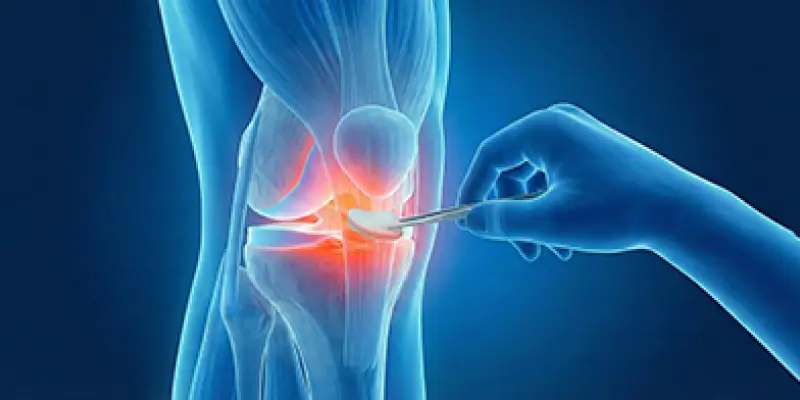

Total diz protezi, ileri osteoartrit ve diz hasarında hasarlı kıkırdak ve kemik yüzeylerinin metal ve polietilen protezle değiştirilmesidir. Endikasyonlar, cerrahi ve rehabilitasyon.

Menisküs onarımı ve nakli, dizde yırtık veya kayıp menisküsün artroskopik cerrahi ile onarılması veya donör menisküs naklidir. Belirtiler, yöntemler ve rehabilitasyon.